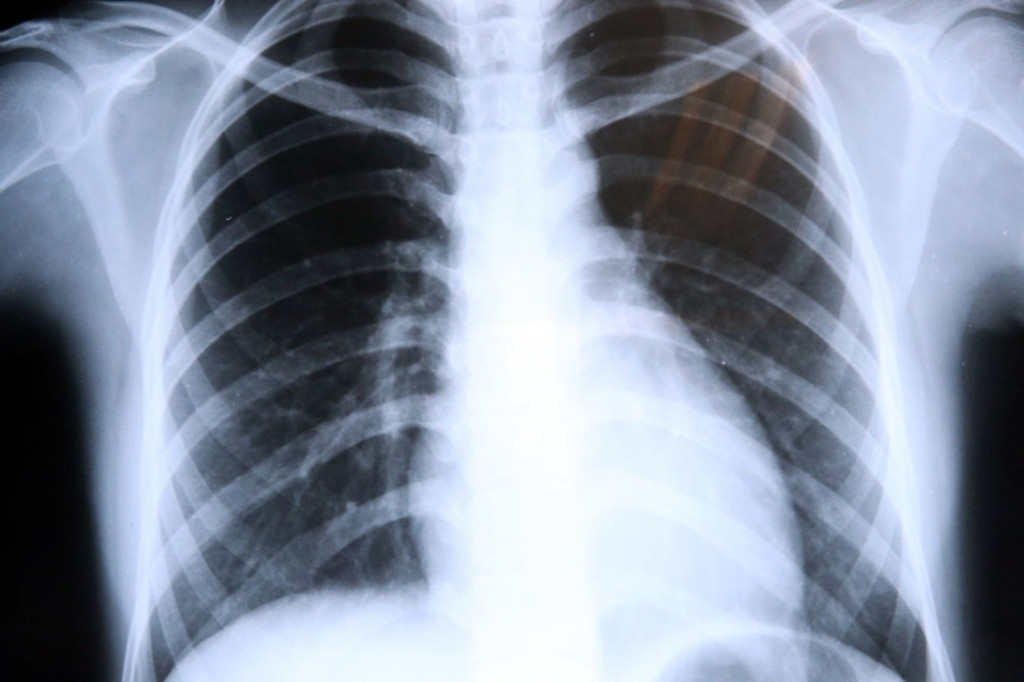

Rak pluća gotovo da ne daje znake upozorenja, a kada se otkrije u kasnoj fazi, šanse za preživljavanje su samo dva odsto, zbog čega se i često naziva ubicom bez najave.

Tumori pluća mogu biti maligni (zloćudni) i benigni (dobroćudni). Rak pluća je zloćudni tumor. Nije zarazna bolest i ne može se preneti sa čoveka na čoveka. U većini slučajeva, rak pluća ne daje nikakve simptome sve dok bolest već ne uznapreduje. Ipak, postoji i mnogo slučajeva u kojima ljudi simptome ove teške bolesti zamenjuju nečim drugim, što je uvek fatalna greška.